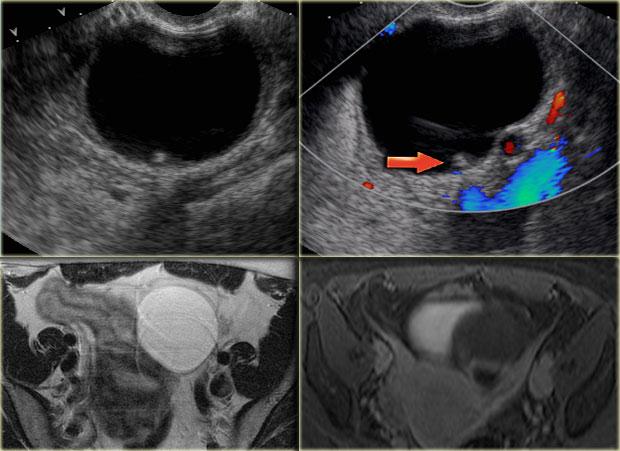

Các hình ảnh siêu âm qua ngã âm đạo cho thấy một nang buồng trứng phức tạp nhỏ với mạch máu thành nang trên phân tích Doppler năng lượng.

Hình ảnh Doppler vòng tròn đặc trưng này được gọi là dấu hiệu ‘vòng lửa’ (ring of fire).

Lưu ý, có hiện tượng xuyên âm tốt và không có mạch máu bên trong, phù hợp với nang hoàng thể đang thoái triển một phần.

Cần nhớ rằng phụ nữ đang dùng thuốc tránh thai thường sẽ không hình thành hoàng thể, vì thuốc tránh thai ngăn chặn quá trình rụng trứng.

Mặt khác, việc sử dụng thuốc kích thích rụng trứng làm tăng nguy cơ hình thành nang hoàng thể.

Một trường hợp khác với hình ảnh điển hình của dấu hiệu ‘vòng lửa’ trên siêu âm.

Trên tiêu bản giải phẫu bệnh, nang xuất huyết xẹp có thể được quan sát rõ ràng.

Nang hoàng thể trên MRI: hình ảnh chuỗi xung T2W mặt cắt ngang cho thấy nang hoàng thể đang thoái triển (mũi tên).

Đây là hình ảnh bình thường.

Buồng trứng phải cũng bình thường.